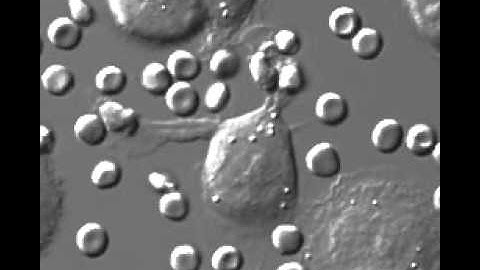

Modeling signaling networks to decode macrophage function